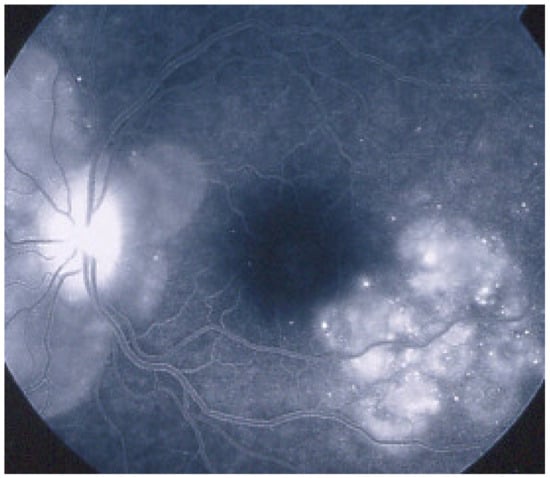

As the affected areas involved are significantly larger than in MEWDS, ICGA hypofluorescence is much more pronounced and widespread (Figure 10). The ischaemic consequences on the retina are also much more important than in MEWDS where ischaemia-induced FA hyperfluorescence remains usually faint. In contrast, in APMPPE/AMIC, FA shows early hypofluorescence due to choriocapillaris non-perfusion. In the later phase of FA, pronounced hyperfluorescence and even pooling occurs due to massively ischaemia-induced increased permeability of both the outer and inner retinal vascular plexuses, which correspond to the yellow discoloured plaques seen on fundus examination (Figure 9). Exudation and pooling in late FA frames can only come from retinal vessels in response to outer retinal ischaemia, as the underlying choroid is non-perfused (Figure 11 and Figure 12). FAF shows hyperautofluorescence in moderately involved areas (loss of photoreceptor outer segments) but hypoautofluorescence in areas with severe vascular drop out. SD-OCT shows loss of photoreceptor outer segments in moderately involved areas. OCTA shows vascular drop-out.

FAEarly hypofluo in diseased areas (non-perfusion) then diffuse hyperfluo/pooling (due to retinal ischaemia) (Figure 12)